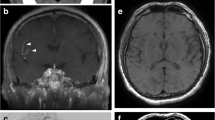

For the patients with intracranial atherosclerosis, the coronal MinIP of VWI showed asymmetrical structures of LSA. The numbers of LSA were 4.3±1.3 on the symptomatic side and 5.0±1.1 on the asymptomatic side. The vessel wall lesion was clearly indicated in the curved-MPR along MCAs. In nine patients, nine plaques were identified on MCA-M1 on the symptomatic side, and three plaques were identified on the asymptomatic side. The combined evaluation of LSA vasculatures and large arterial lesions was, therefore, available via a single VWI scanning in about 8 minutes. Figure 6 demonstrated an example of the vessel wall lesion on MCA and the impaired LSA on the ipsilateral side, compared with a healthy subject.

The reconstructed images of a 37-year-old female healthy volunteer (a,b) and a 62-year-old female with an acute infarction in right basal ganglia (c,d). a The curved-MPR showed no thickening of MCA wall in both sides. b Coronal MinIP revealed symmetrical LSAs of the left and right hemispheres. c The curved-MPR showed a plaque with hyperintensity (yellow line) on the MCA wall. d Coronal MinIP revealed decrease of right LSA branches compared to the left side (yellow arrow)